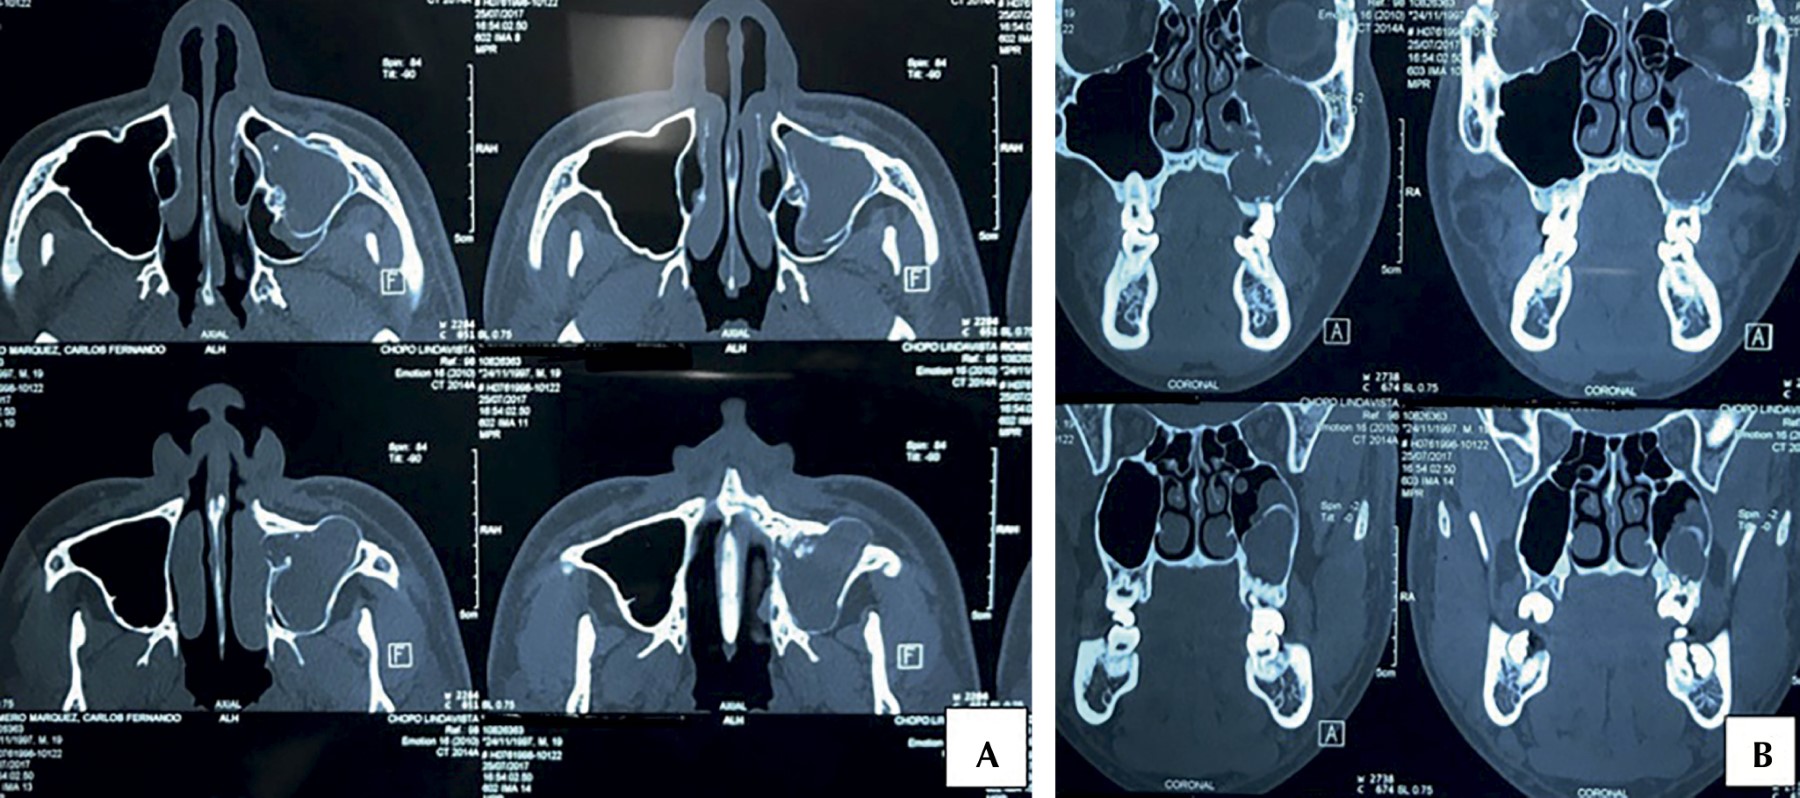

The calcifying odontogenic cyst is defined as a cystic lesion of benign origin originating from epithelial remains during odontogenesis, it presents as an asymptomatic and slow growthing lesion, which affects the anterior region of the mandible and the maxilla, it is frequent in young adults of the third to the fourth decade, without predilection for gender. It is rare, constituting only 0.37% to 2.1% of all odontogenic cysts and tumors. 65% occur in the incisor region of both jaws and approximately 20% are associated with an odontoma. Histologically, its generally composed of a cystic cavity with a fibrous capsule lined with odontogenic epithelium. The typical microscopic feature of this lesion is the presence, in varying numbers, of aberrant anucleated epithelial cells, called "ghost cells". The treatment is enucleation. We present the case of a 20-year-old male with a diagnosis of Gorlin's cyst in the left maxillary sinus and surgical treatment that consisted of enucleation of the lesion

Figure 3

Figure 4